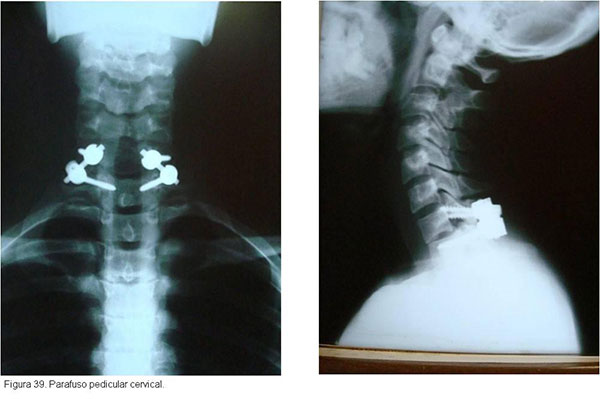

As fraturas cirúgicas da região cervical são estabilizadas com amarrilhos, placas e parafusos, sempre associados à enxertia óssea para facilitar a artrodese. O uso de estabilização anterior e/ou posterior depende do tipo de fratura.(figuras 37, 38, 39)